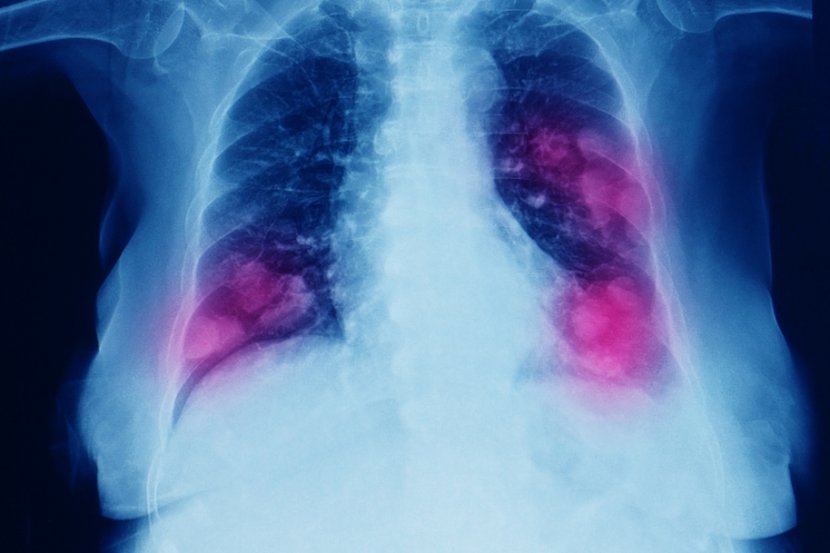

Najčešća mesta, odnosno organi na koje se primarni rak u vidu metastaza širi jesu kosti, jetra i pluća

Rak se može proširiti gotovo na bilo koji deo tela, iako je veća verovatnoća da će se različite vrste raka širiti na određena područja od drugih. Najčešća mesta, odnosno organi na koje se primarni širi jesu kosti, jetra i pluća. Evo nekih uobičajenih modela širenja raka sa primarnog mesta nastajanja na ostale organe, ne uključujući limfne čvorove:

• pluća: nadbubrežna žlezda, kosti, mozak, jetra, druga pluća

• kratak dah (kada se rak proširio na pluća)